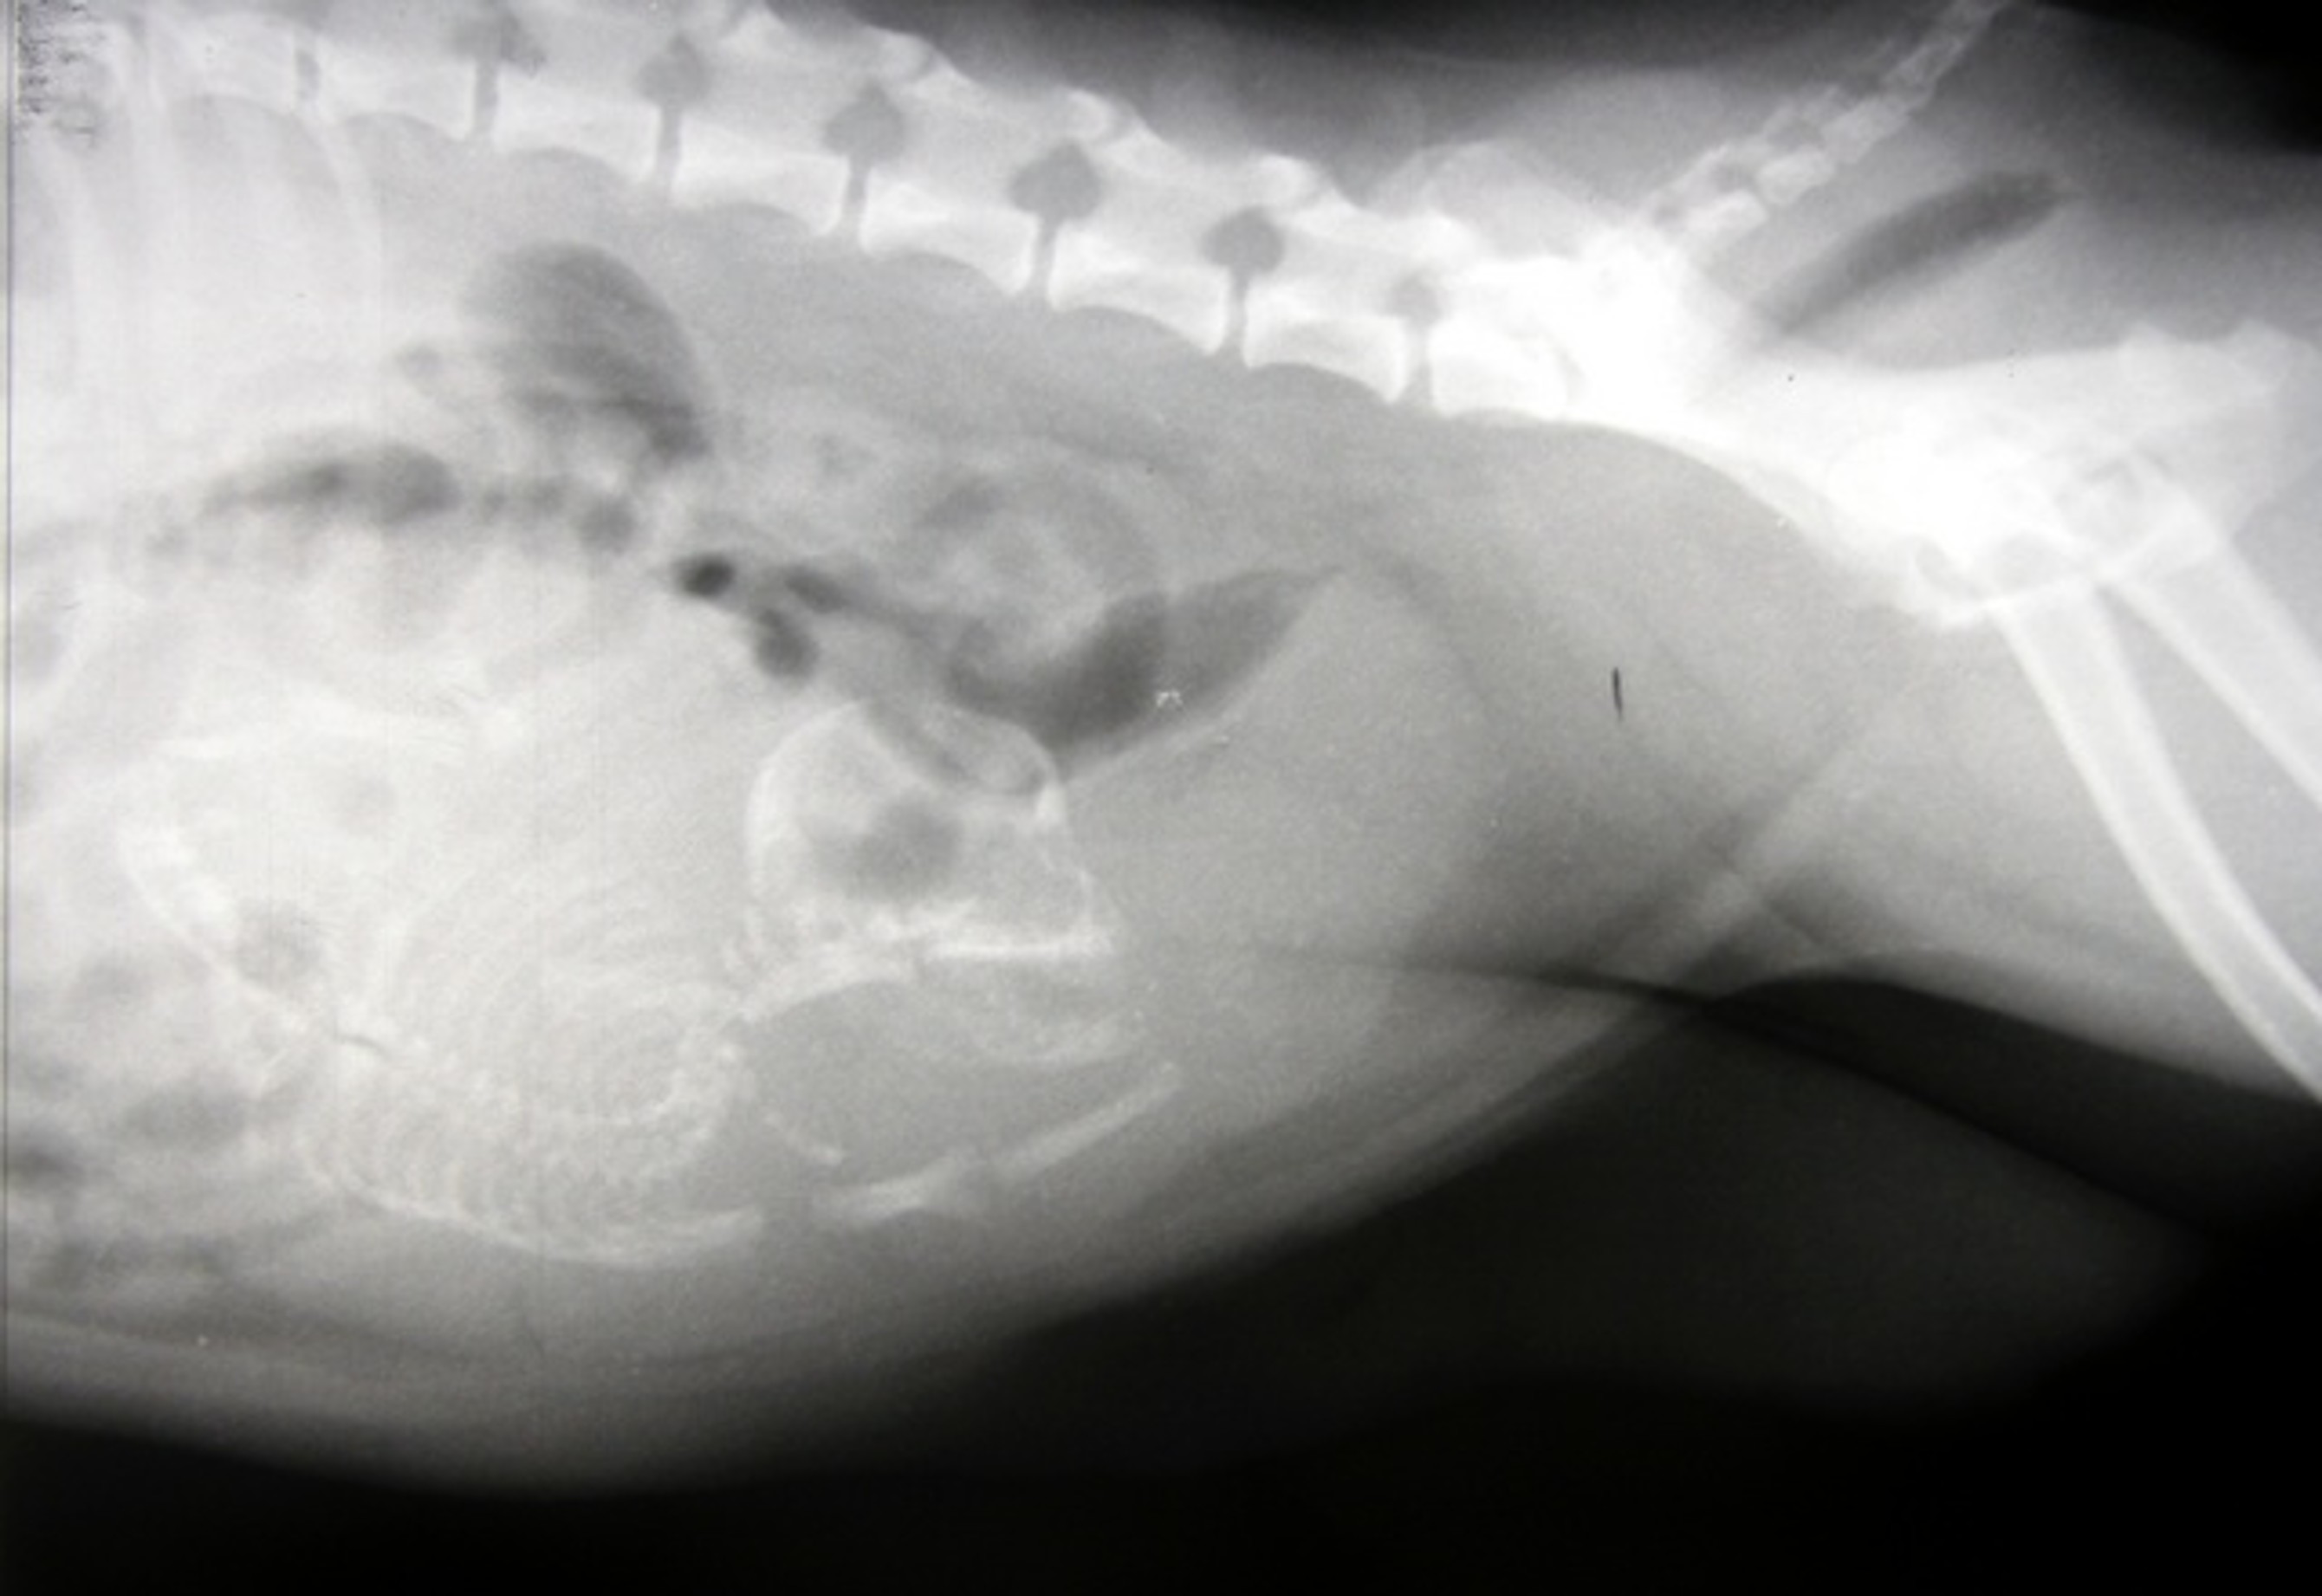

Radiography - Diaphragmatic hernia